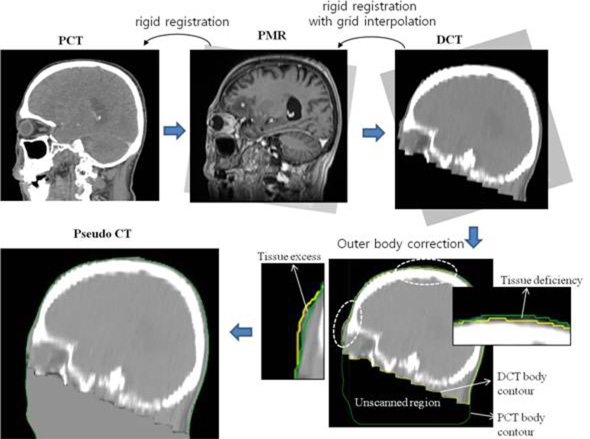

Inter-image differences may arise, even when using the same patient’s scan set. This error should be also corrected for exact dose calculation, but the correction cannot be made with the rigid image registration technique. To simplify this problem, we assumed that all inter-image differences between brain scans occur in the outer skull region, whereas internal anatomic changes would be negligible for adult patients. Using this assumption, the inter-image differences for the outer skull region were simply corrected by matching the outer body alone, as schematically displayed in Figure 4.

Figure 4: Work flow for pseudo-CT generation method used in the study.

The step-by-step flow for image processing is described below and schematically illustrated in Figure 4. First, the PMR scan was rigidly fused or reoriented with respect to the PCT scan until the bony structures of the skull on the two scans were best matched. Second, the rigid registration of DCT scan was applied to the reoriented PMR scan. Third, the reoriented DCT scan was interpolated to have the same grid size as the PMR scan. Fourth, the external body contours of the DCT and PCT scans were delineated based on CT pixel density. Finally, the tissue excesses and deficiencies of the DCT scan with respect to the referenced PCT scan were corrected so that both scans had the same outer body shape. In detail, the pixel regions in the DCT scan that were located outside the PCT body contour were defined as the tissue-excessive regions and their pixel CT values were corrected to the air-equivalent value (-1000 HU). Regions within the PCT body contour but outside the DCT body contour were defined as the tissue-deficient regions and their CT values were assigned the soft tissue-equivalent value (0 HU). Some unscanned tissues in the ordinary DCT scan (see Figure 4) were also included as tissue deficiencies and corrected to 0 HU with no consideration of their real CT electron density.

Once the above steps are complete, the DCT scan has the same skull orientation as the PCT (and also reoriented PMR) scan, and has the same outer body shape as the PCT scan. Corrected DCT scans are described as post-generated pseudo CT scans and used here to calculate 3D dose distributions.